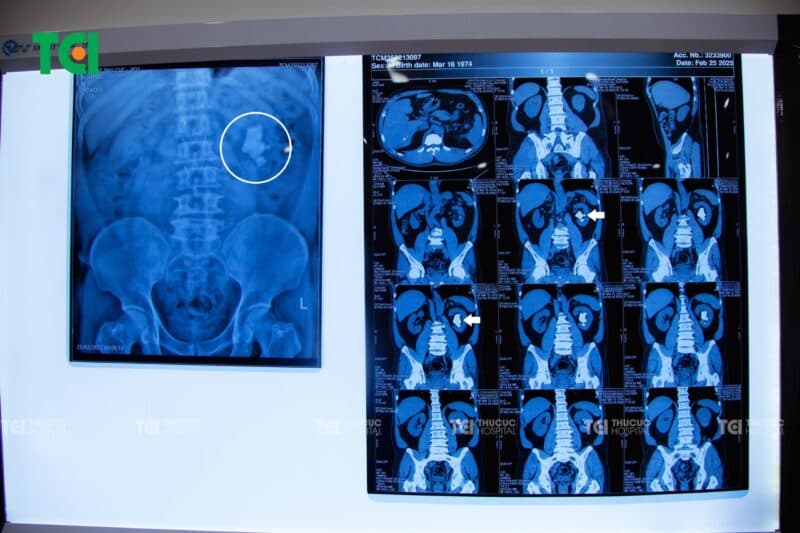

Nhập viện vì cơn tai biến mạch máu não nhẹ cách đây hai tháng, anh N.H.B (51 tuổi, Bắc Ninh) không ngờ rằng trong quá trình kiểm tra, phát hiện một “tảng đá” khổng lồ án ngữ trong thận trái – khối sỏi san hô có kích thước lên đến 38x50x20mm, gần như bao trọn toàn bộ nhu mô thận.

Hình ảnh sỏi san hô kích thước hơn 5cm trong thận của bệnh nhân N.H.B